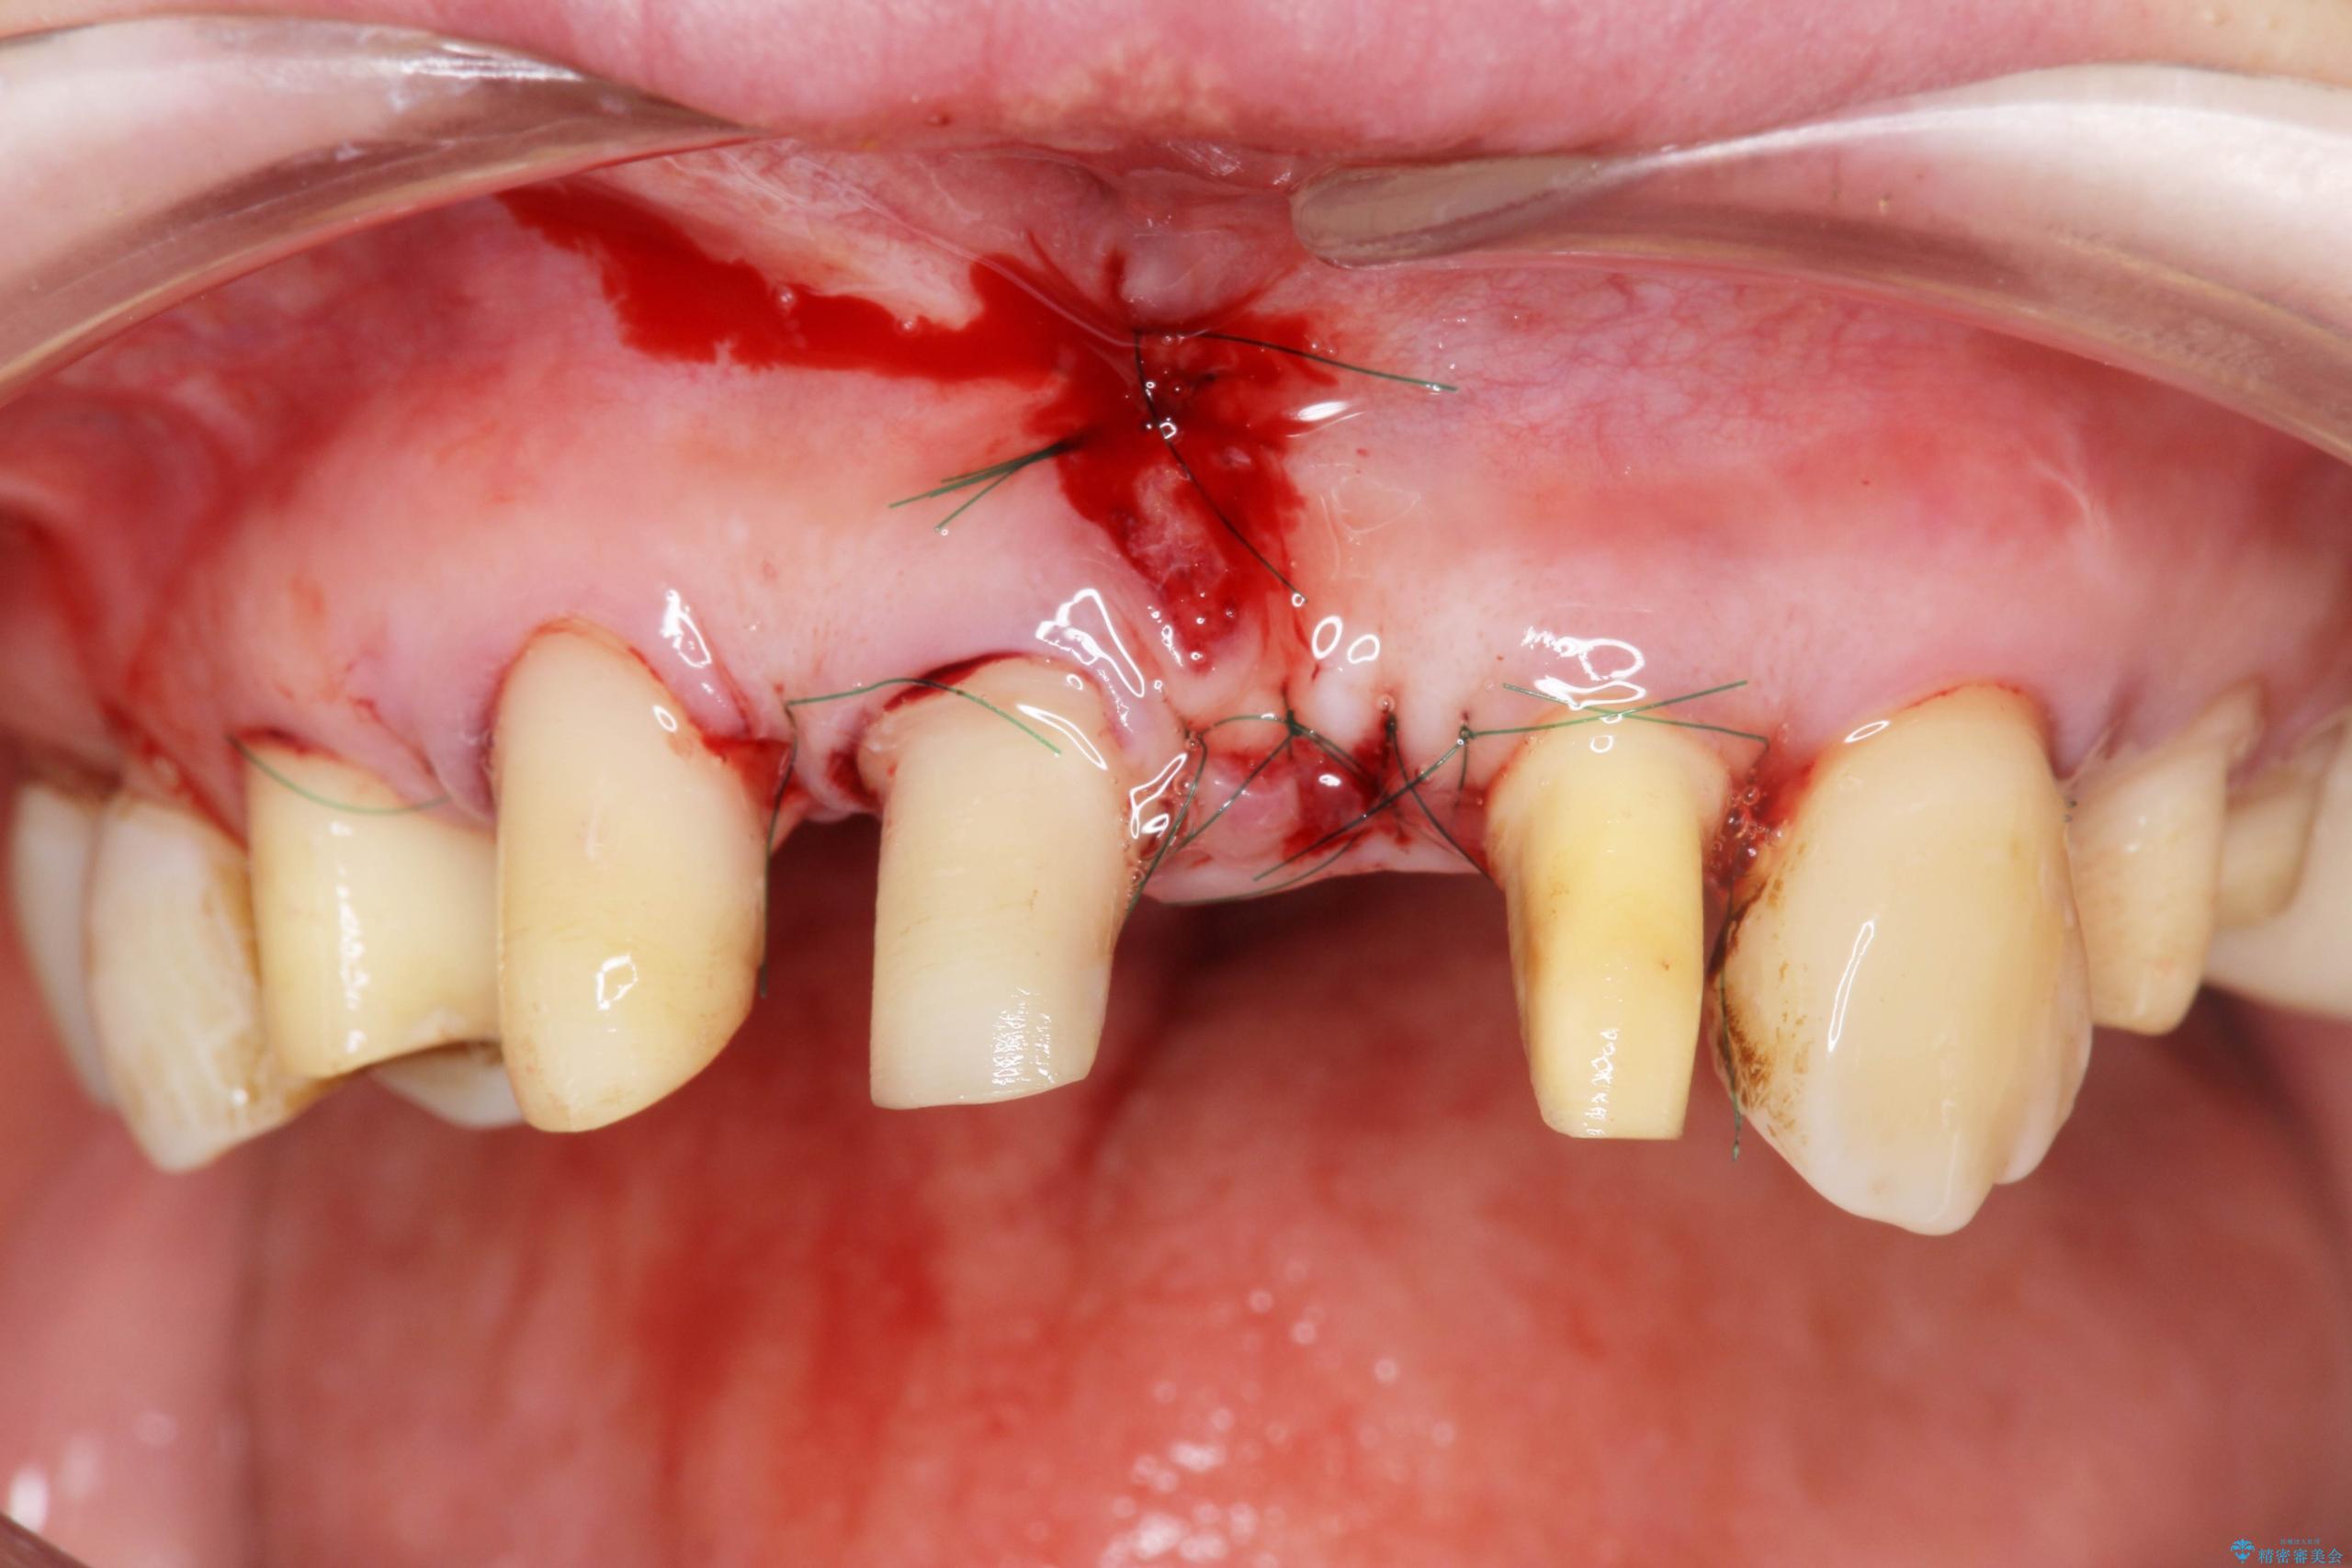

まず、保存の難しい歯を抜去したのち矯正治療を行い歯並びの改善、歯周ポケットを除去したことで安定した歯周環境、咬合関係を作り出すことができました。

治療中

歯の総合的なマネージメントを行う包括的歯科治療の実践[ 歯周病・矯正・セラミック補綴 ] 治療中画像 歯の総合的なマネージメントを行う包括的歯科治療の実践[ 歯周病・矯正・セラミック補綴 ] 治療中画像 歯の総合的なマネージメントを行う包括的歯科治療の実践[ 歯周病・矯正・セラミック補綴 ] 治療中画像 歯の総合的なマネージメントを行う包括的歯科治療の実践[ 歯周病・矯正・セラミック補綴 ] 治療中画像 歯の総合的なマネージメントを行う包括的歯科治療の実践[ 歯周病・矯正・セラミック補綴 ] 治療中画像 歯の総合的なマネージメントを行う包括的歯科治療の実践[ 歯周病・矯正・セラミック補綴 ] 治療中画像 歯の総合的なマネージメントを行う包括的歯科治療の実践[ 歯周病・矯正・セラミック補綴 ] 治療中画像 歯の総合的なマネージメントを行う包括的歯科治療の実践[ 歯周病・矯正・セラミック補綴 ] 治療中画像 歯の総合的なマネージメントを行う包括的歯科治療の実践[ 歯周病・矯正・セラミック補綴 ] 治療中画像 歯の総合的なマネージメントを行う包括的歯科治療の実践[ 歯周病・矯正・セラミック補綴 ] 治療中画像 歯の総合的なマネージメントを行う包括的歯科治療の実践[ 歯周病・矯正・セラミック補綴 ] 治療中画像